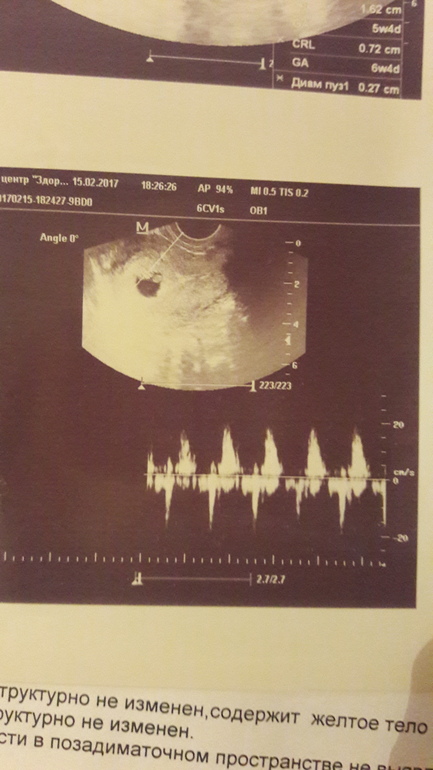

Привет девочки!!! Позавчера сижу на обеде и как схватило бок левый. Я бегом в клинику звонить. Записей нет((( я в трубку реву... соединили с врачем,сказала чтоб презжала пол шестого. Всю трясет как осиновый листочик. Презжаю...ложусь на кушетку...врач говорит: "маточная беременность. Видишь пульсирует?" А я ничего не вижу в голове только маточная беременность!!! И тут она звук включает. Сердечко!!! Слезы счастья сами текут!!!

На узи позавчера. Срок по месячным 6+4.

Срок 6,4 по месячным. Я особо не вникала в размеры. Главное, что гиня сказала ,что хорошо развиваемся и соответствуем сроку.

Вы про пол? Он 7 мм, невозможно что то увидеть))